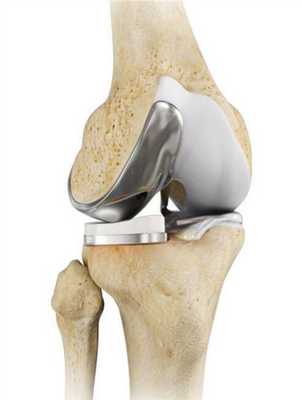

Какие бывают эндопротезы?

Протезные системы бывают с подвижной или неподвижной платформой, а также предусматривающие сохранение или удаление задней крестообразной связки. Различаются по виду фиксации, она может быть цементной, бесцементной и комбинированной.

- Подвижные и неподвижные платформы. Большинству пациентов ставят имплантат с амортизирующим вкладышем, который плотно связан с большеберцовым элементом, то есть изделия с неподвижной платформой. Наличие же мобильного вкладыша внутри металлического большеберцового компонента требует хорошего состояния мышечной системы и капсульно-связочного аппарата, в противном случае может произойти смещение протеза.

Самый распространенный тип импланта коленного сустава.